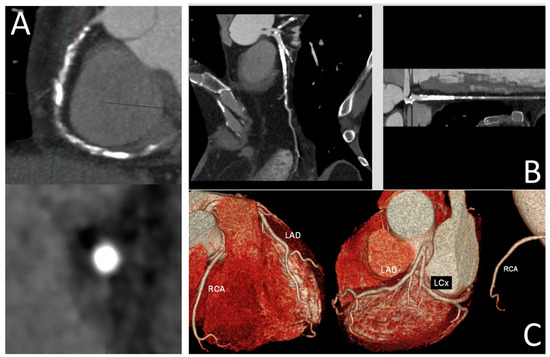

- Panuccio, G.; Werner, G.S.; De Rosa, S.; Torella, D.; Leistner, D.M.; Siegrist, P.T.; Haghikia, A.; Skurk, C.; Mashayekhi, K.; Landmesser, U.; et al. Full-Moon Coronary Calcification as Detected with Computed Tomography Angiography in Chronic Total Occlusion Percutaneous Coronary Intervention. Am. J. Cardiol. 2024, 222, 149–156. [Google Scholar] [CrossRef] [PubMed]

- Panuccio, G.; Skurk, C.; Landmesser, U.; Abdelwahed, Y.S. Double “Full Moon” CTO Plaque Detected by Computed Tomography Could Predict High-Grade Debulking Techniques: A Case-Report. Clin. Case Rep. 2023, 11, e7325. [Google Scholar] [CrossRef] [PubMed]